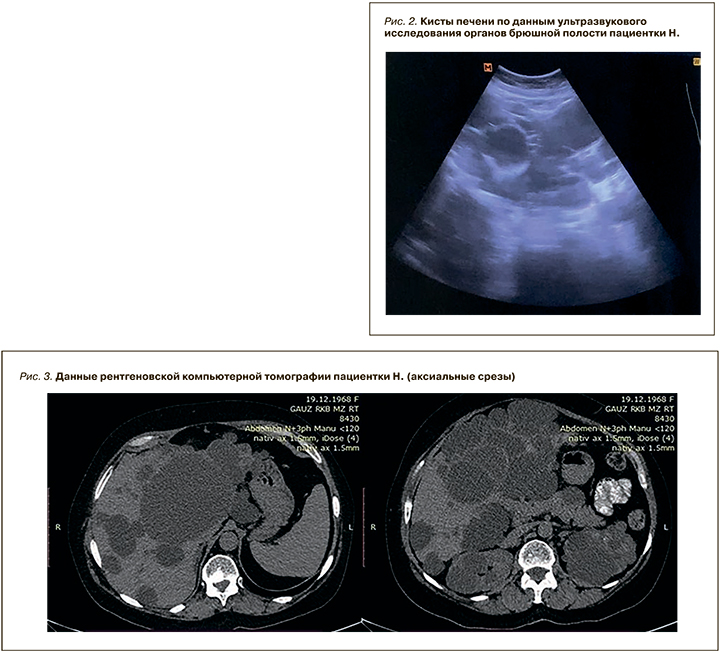

Результаты УЗИ ОБП: размеры печени увеличены за счет множественных тонкостенных образований с максимальным диаметром 95 мм (рис. 2). В брюшной полости свободная жидкость не визуализируется. Обе почки представлены множественными тонкостенными образованиями с максимальным диаметром слева 52 мм, справа – 39мм.

Данные рентгеновской компьютерной томографии (рис. 3): структура печени неоднородна за счет множественных жидкостных образований различных размеров, максимально до 122 мм. Обе почки деформированы за счет жидкостных образований с максимальным размером до 56 мм. Свободная жидкость не обнаружена.